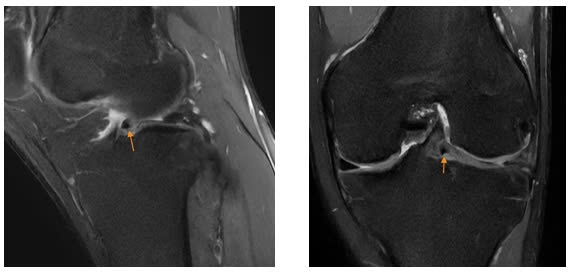

Trên những hình ảnh cộng hưởng từ, bác sĩ và chuyên gia của Trung tâm chẩn đoán hình ảnh ghi nhận 5/6 dấu hiệu đặc trưng của rách quai xô điển hình: mất hình nơ sụn chêm, mảnh sụn rời trong khuyết gian lồi cầu, sụn chêm lật, hai sừng trước và sừng sau nhô bất thường. Hình ảnh cho thấy rách phức tạp ở thân và sừng sau sụn chêm ngoài, với mảnh sụn di lệch vào ổ khớp.

| Hình ảnh chấn thương đầu gối của bệnh nhân |